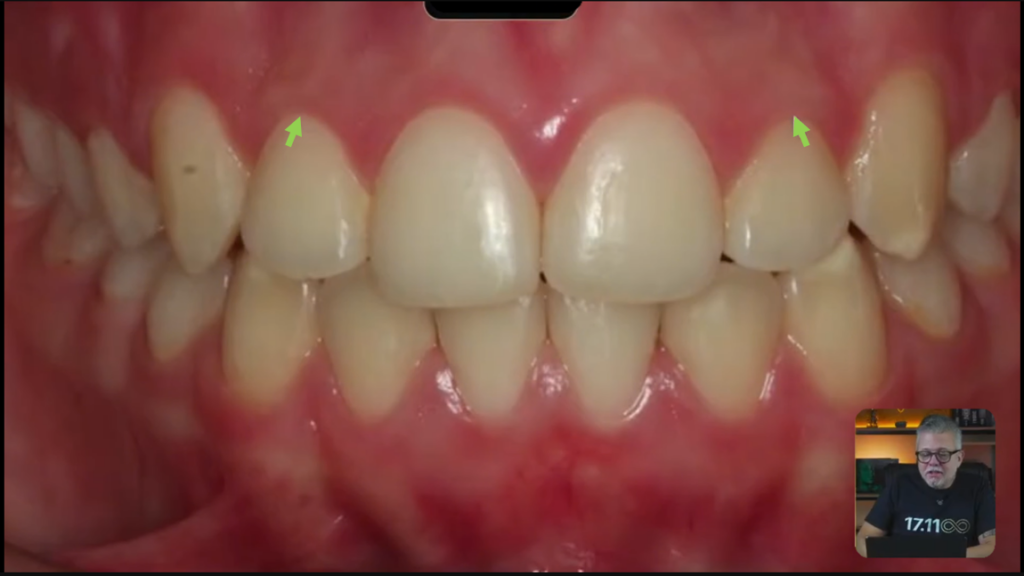

Vocês estão vendo que ela está de classe 1, do lado direito e do lado esquerdo?

Quando você tem uma paciente de classe 1 dos dois lados e você tem bastante apinhamento, você pode até pensar em tirar pré-molares.

Olha o zênite desse lateral e olha desse lateral aqui:

Vocês estão vendo esse canino aqui, que tem um espacinho aqui atrás:

Quando esse paciente pega essa mandíbula dele, os dentes inferiores, e ele faz o movimento de lateralidade, esse canino inferior, pessoal, ele não toca imediatamente no canino superior.

Então, não faz a desoclusão imediata.

Todo caso que você terminar tem que fazer a desoclusão imediata, porque senão os dentes posteriores vão ficar com um contato ou então um movimento no sentido látero-lateral.